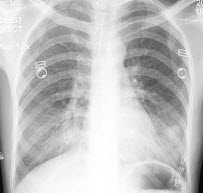

女,31岁,咳嗽发热1周,胸片检查如图,最可能的诊断是()

A.两肺结核

B.两肺炎症

C.两侧胸膜炎

D.两肺不张

E.慢性支气管炎